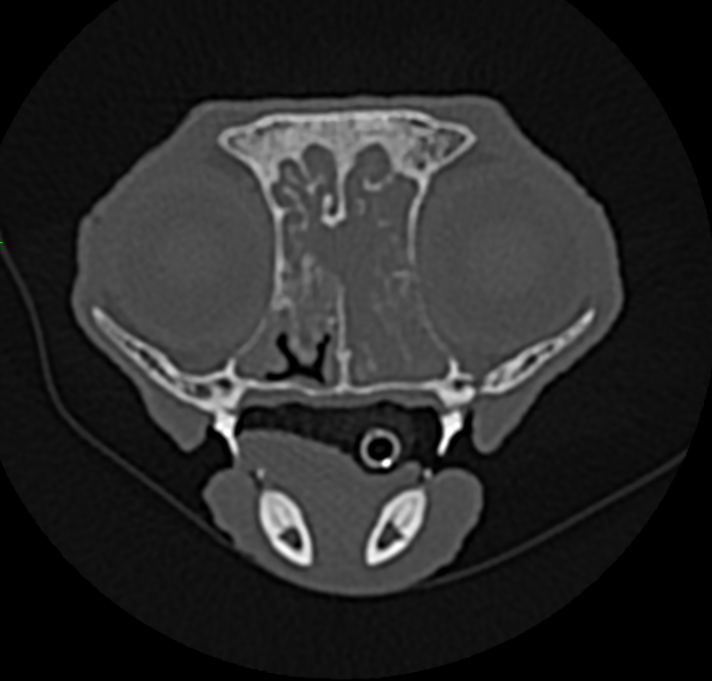

CT-scan #

De beelden van de CT-scan toonden aan dat Gust te kampen had met een verhoogde hoeveelheid slijmen en verdikking van de slijmvliezen. Daarnaast werd er gezien dat de beenderige structuren eveneens waren aangetast. Op basis van deze bevindingen werd er gedacht aan een erge chronische ontsteking, mogelijks ten gevolge van een schimmel.